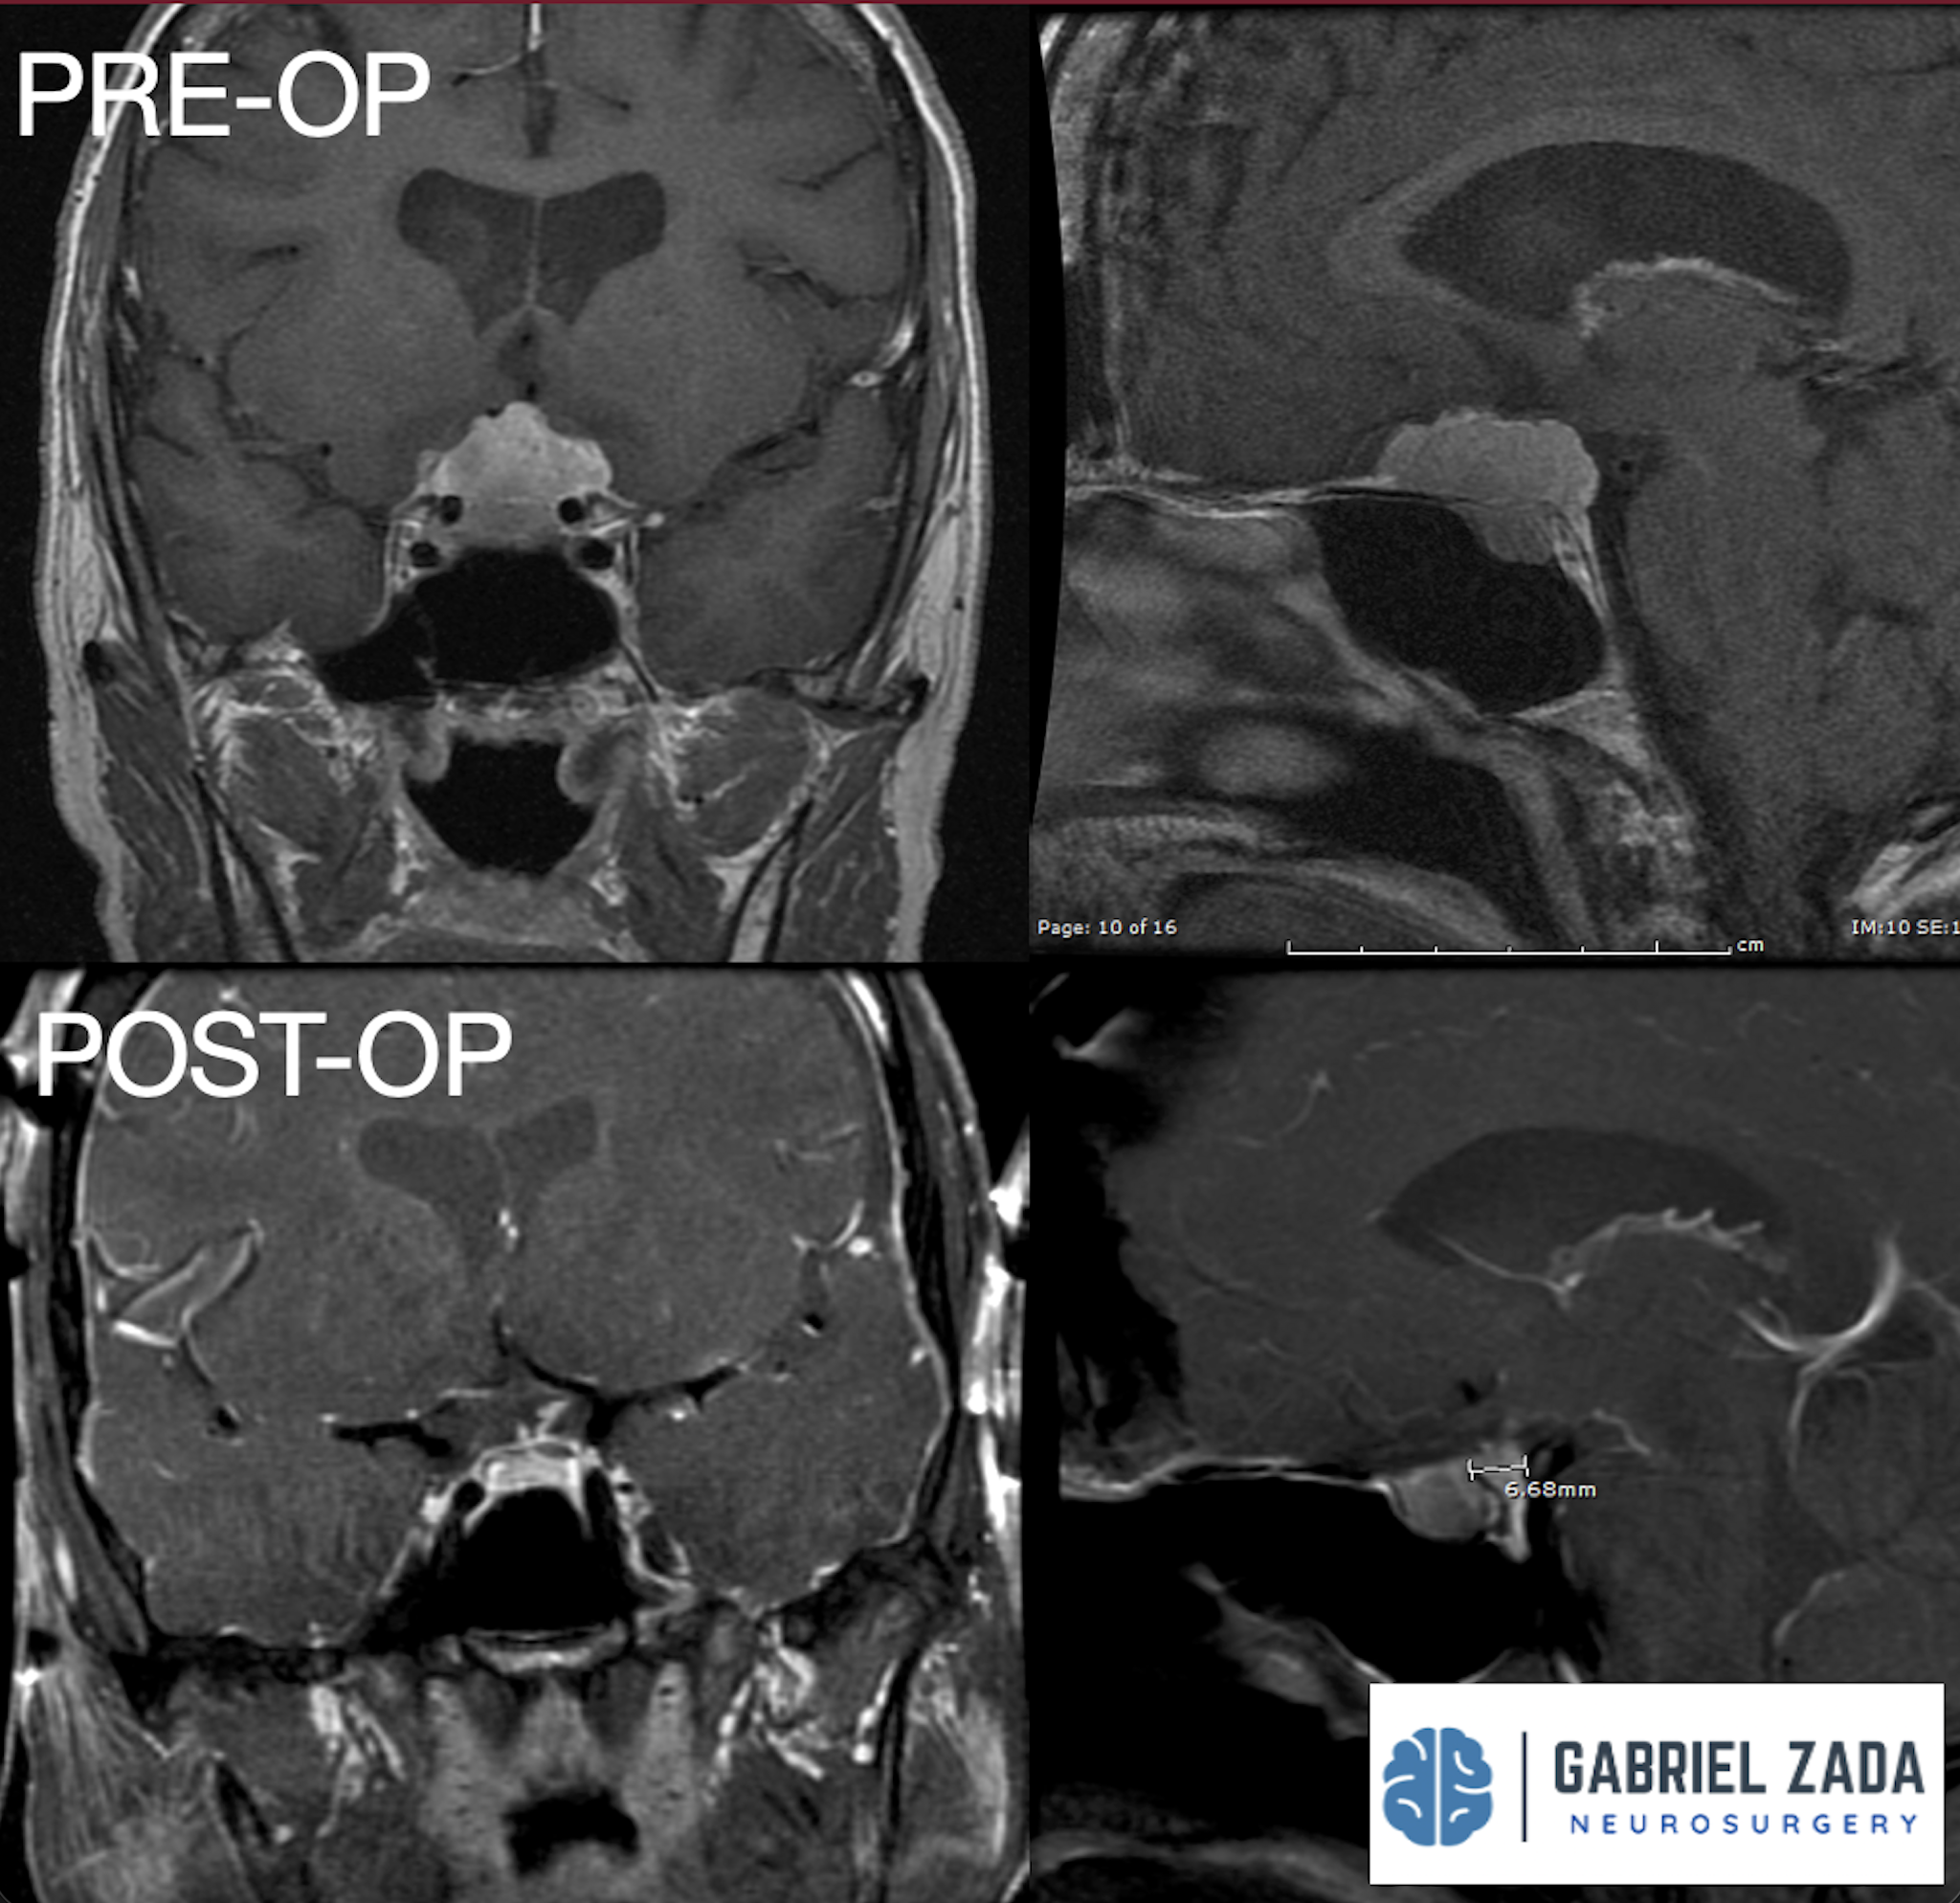

Explore this comprehensive gallery featuring pre‑ and post‑operative imaging of patients with skull‑base tumors treated by Gabriel Zada, MD, MS, FAANS, FACS. These cases highlight Dr. Zada’s expertise in advanced neurosurgical techniques and outcomes.

*Representative cases shown for educational purposes. All images de-identified. Individual results vary.